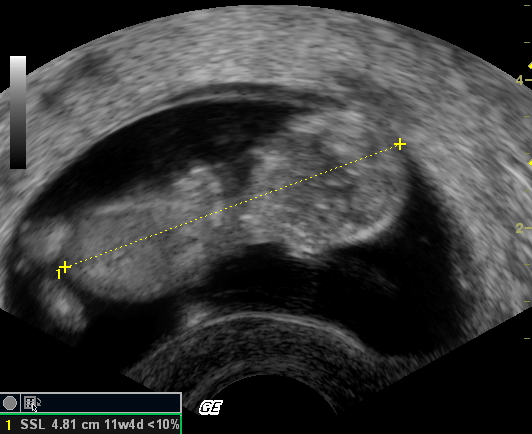

Dann war wieder Fototermin:

Jetzt hat Mam so einen Mutterpass. Da stehen lauter komische Daten und Eintragungen über mich drin. Leider hat niemand meiner Mami erklärt, was die denn zu bedeuten haben. Zum Glück gibt es ja Papa und das Internet...

Demnach sind wir jetzt in der 12ten Schwangerschaftswoche und ich bin 4,81 cm gross. Man bin ich gewachsen. Mam hör ich immer reden, dass sie sich gar nicht vorstellen kann, dass ich jetzt schon fast 5 cm gross in ihr bin. Wenn die wüsste, dass ich mich noch viel breiter bei ihr machen werde...

Was Mami auch sehr beruhigt ist die Tatsache, das ich allein in ihrem Bauch bin, nix da mit Zwillingen oder dergleichen... Jedenfalls hab ich noch niemand weiter hier im Bauch entdeckt und die Ärztin hat ja auch ziemlich genau geschaut...

Die Ärztin hat nun auch einen Geburtstermin errechnet, demnach müsste ich am 17-06-2008 Mamas Bauch verlassen. Mal sehen... |